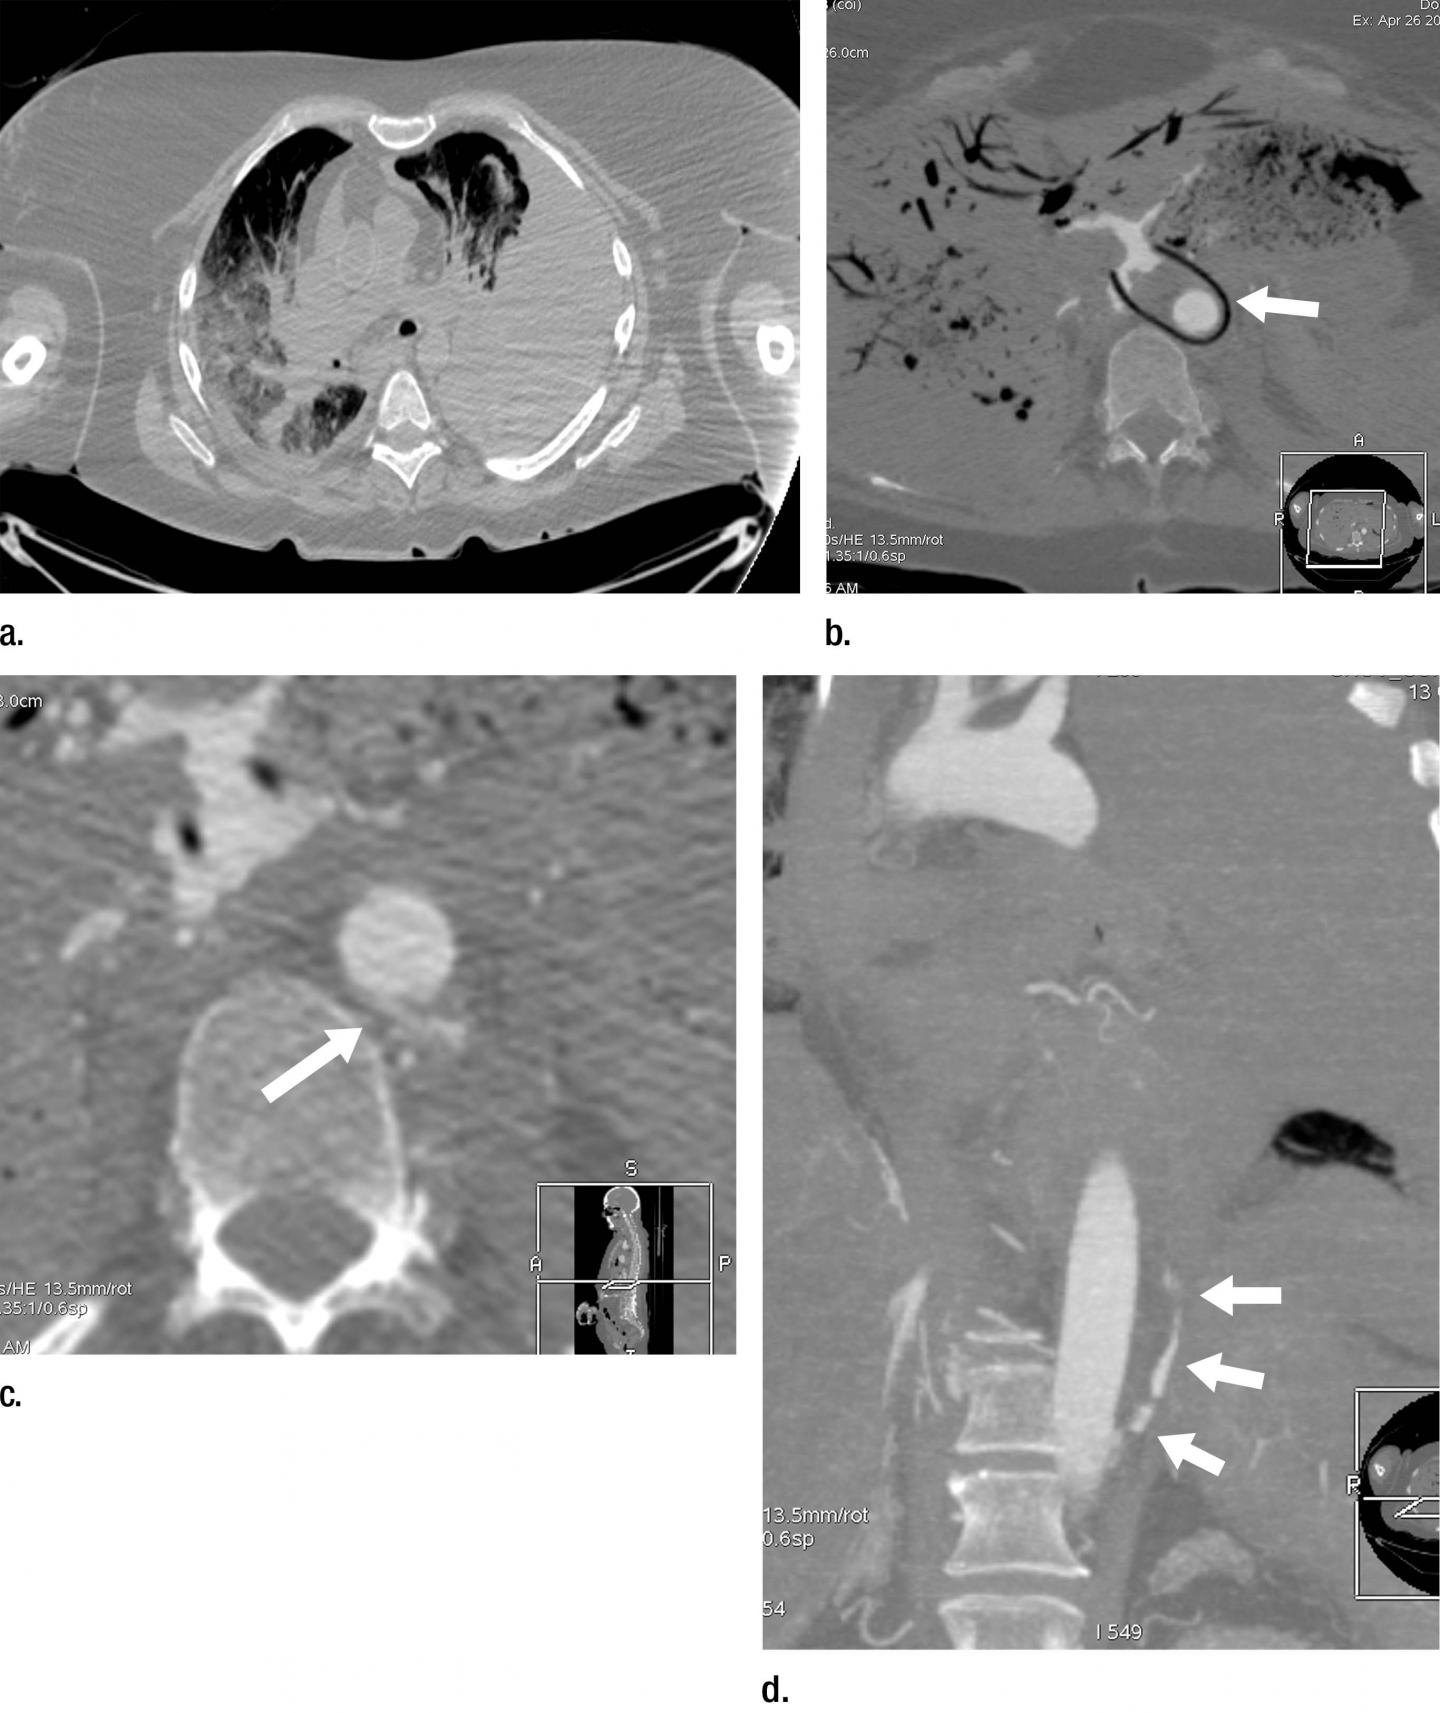

Modern imaging techniques like CT and MRI are often used in forensic pathology. However, post-mortem CT is limited by relatively low soft tissue contrast and poor visualization of the vascular system. A technique known as post-mortem CT angiography, or PMCTA, was developed to address those limitations by introducing contrast agent into the body.

PMCTA was significantly superior to autopsy at identifying skeletal and vascular lesions, or areas of damage in the bones and blood vessels. PMCTA identified 96 percent of skeletal lesions and 94 percent of vascular lesions, compared with 65 percent for autopsy. These lesions can provide important information in post-mortem examinations, Dr. Grabherr said.

"The combination of bone lesions and vascular lesions is especially seen in cases of traumatic death, such as falls from height, traffic accidents, ballistic trauma and sharp trauma in homicides and suicides," she said. "This means that PMCTA is an excellent choice to investigate such cases and can be used combined with or even independently of conventional autopsy for investigating in these cases."